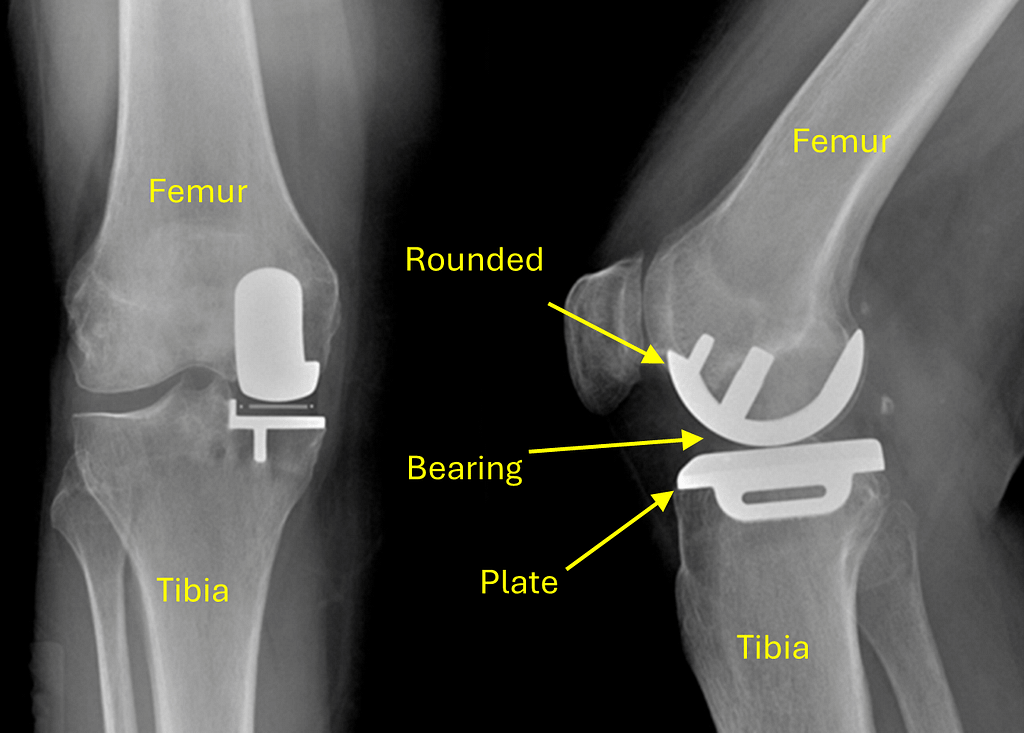

A Unicompartmental Knee Replacement can be thought of as a reconstruction of the worn side of the knee. As shown on the X ray here, the tibial surface is resurfaced with a thin flat metal plate, and the femoral surface is replaced by a rounded metal surface. A plastic insert, known as a bearing, is placed between the two metal surfaces to allow them to move against each other.